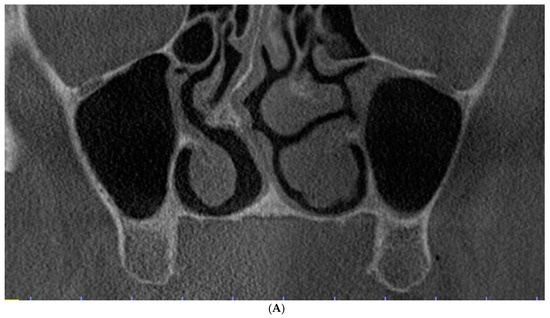

Class 0: There is an adequate sub-sinus residual bone height, which is not indicated for direct maxillary sinus elevation (Figure 2A). The incidence of this finding was 4%.

Figure 2.

Evaluation of the maxillary sinus based on cone beam computed tomography (CBCT) scans in the coronal view. (A) Class 0: Adequate sub-sinus alveolar bone height. (B) Class 1: Reduced sub-sinus alveolar bone height with a thin lateral wall. (C) Class 2: Reduced sub-sinus alveolar bone height with comparable thickness of the lateral and palatal walls. (D) Class 3: Reduced sub-sinus alveolar bone height with a thin palatal wall.

Class 1: There is a reduced sub-sinus residual bone height with a thinner lateral sinus wall in comparison to the palatal wall (Figure 2B), which can be indicated for the lateral window osteotomy technique because buccal access is presumably easier. The crestal window osteotomy technique can also be applied. The incidence of such variant was common (44%).

Class 2: There is a reduced sub-sinus residual bone height with the lateral and palatal sinus walls having a comparable thickness (Figure 2C), which can be indicated for either lateral or palatal window osteotomy. The crestal window osteotomy technique can be utilized as well. This variant was evident in almost half of the obtained scans (49%).

Class 3: There is a reduced sub-sinus residual bone height with a thinner palatal sinus wall in comparison to the lateral wall (Figure 1 and Figure 2D), which can be indicated for the palatal window osteotomy technique or crestal window osteotomy technique. This was the most uncommon variant (3%), which might be logical as the palatal bone is usually denser and thicker [21].

The most common variant was the comparable thickness of the lateral and palatal sinus walls (Figure 2C), in which either the lateral, palatal, or crestal window osteotomies can be applied (49%).